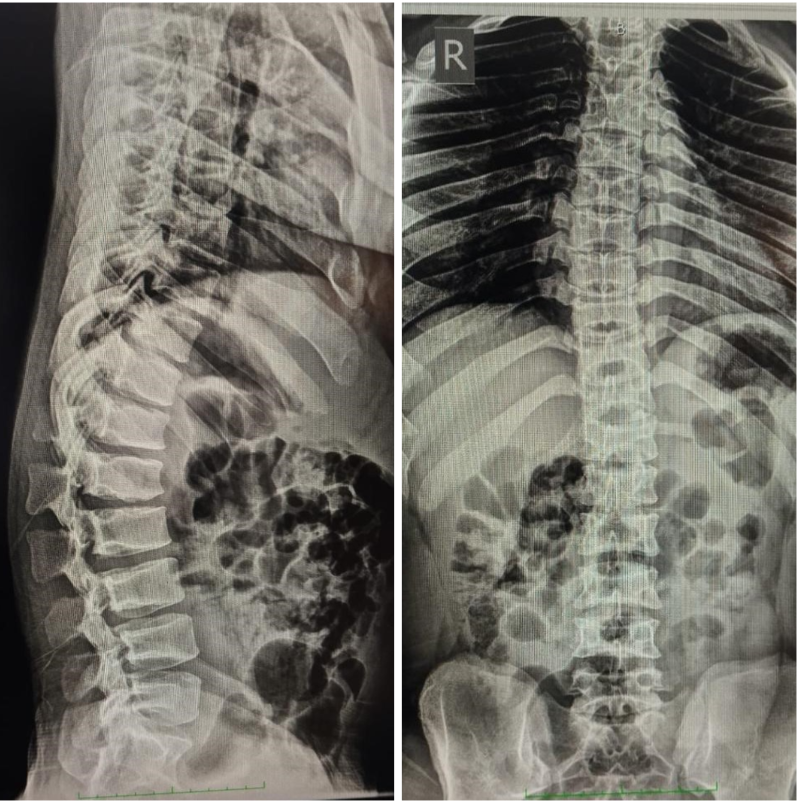

Radiological evaluation included plain radiographs, which showed reduced interpedicular distance and short pedicles in the lumbar spine, consistent with congenital canal stenosis (Fig. 2). Computed tomography confirmed the presence of short pedicles without evidence of ossified ligamentum flavum (Fig. 3). Magnetic resonance imaging demonstrated multilevel lumbar stenosis from L1 to L5 with thickened ligamentum flavum. Pre-operative Oswestry disability index score was 60%. Routine laboratory investigations were within normal limits.

Figure 2: Pre-operative X-ray.